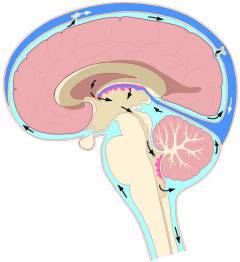

В нормальных условиях головной мозг окружен спинномозговой жидкостью, которая заполняет его внутренние полости — мозговые желудочки — и пространство вокруг него.

Объем спинномозговой жидкости стабилен: у взрослого человека составляет около 150 мл, у детей — меньше и зависит от возраста.

Спинномозговая жидкость образуется в основном в мелких сосудах стенок мозговых желудочков. У взрослого человека вырабатывается примерно 0,35 мл в минуту, что составляет около 500 мл в сутки. Это количество должно всасываться в вены мозга для постоянного обновления жидкости.

Давление спинномозговой жидкости колеблется в пределах 70-180 мм рт. ст. у взрослых, у детей — ниже, в зависимости от возраста.

Гидроцефалия возникает при несоответствии между количеством вырабатываемой и всасываемой спинномозговой жидкости по различным причинам.